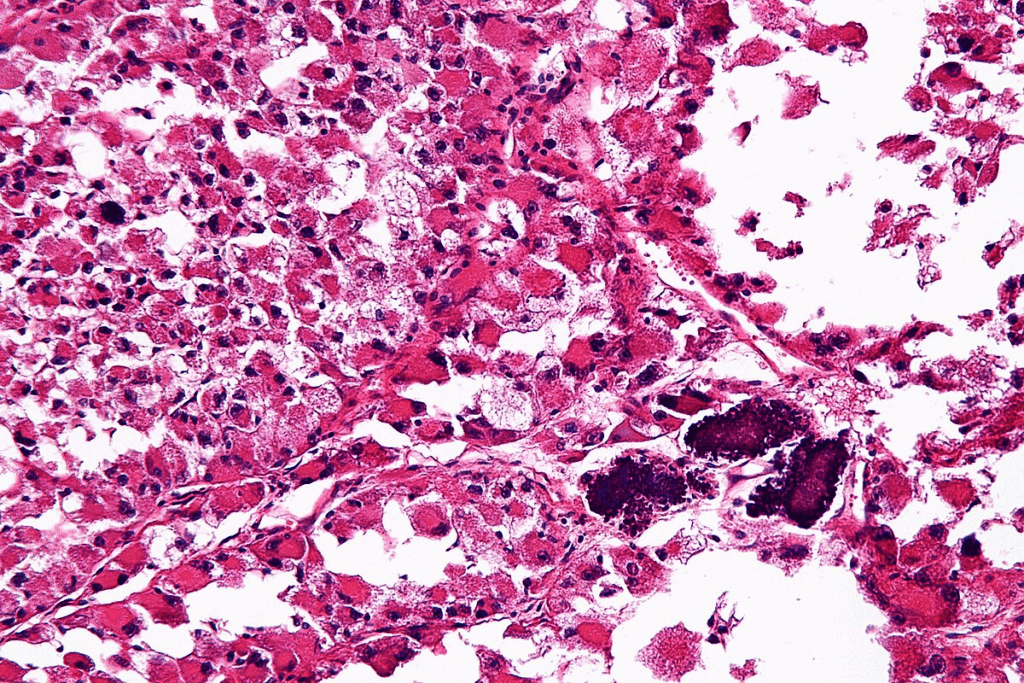

Definition and Classification of Rhabdomyosarcoma

Rhabdomyosarcoma is divided into several types based on how it looks under a microscope. The two main types are embryonal and alveolar rhabdomyosarcoma. Embryonal is more common in young kids, while alveolar is seen in older kids and teens.

Pathogenesis of Rhabdomyosarcoma

Rhabdomyosarcoma pathogenesis is complex. It involves many cellular and molecular changes. Knowing these changes is key to finding effective treatments.

Cellular Origin

Research has focused on where rhabdomyosarcoma comes from. It’s believed to start from muscle precursor cells with genetic changes. These cells stop growing at different stages, making rhabdomyosarcoma diverse.